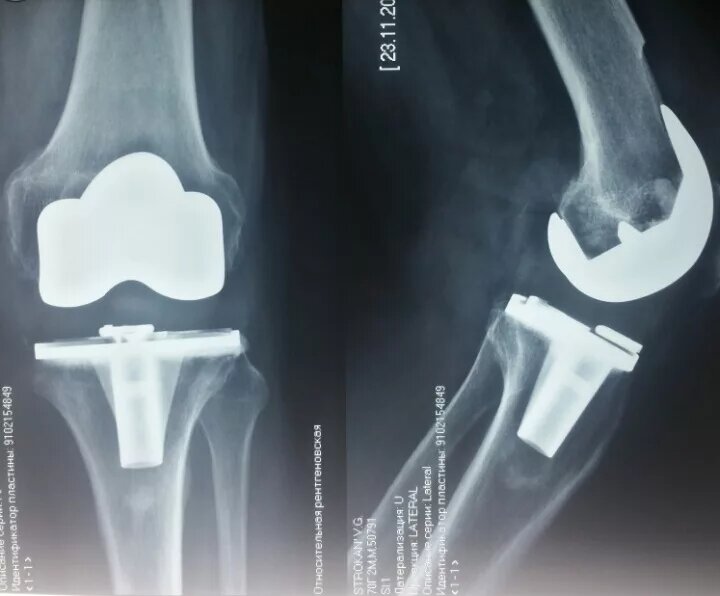

Эндопротез коленного сустава. Фото из интернета